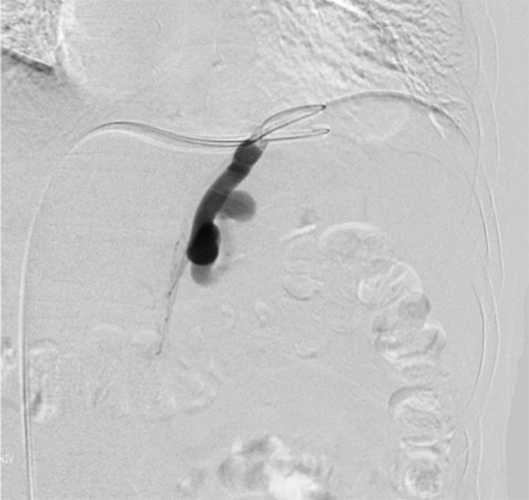

経皮経肝門脈造影

門脈および供血路、食道静脈瘤が描出されている。

出典

img

1: 著者提供